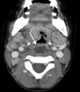

Thoracic extension of neck abscess

Mediastinitis is inflammation of the tissues in the mid-chest, or mediastinum. It can be either acute or chronic. [Source: Wikipedia ]